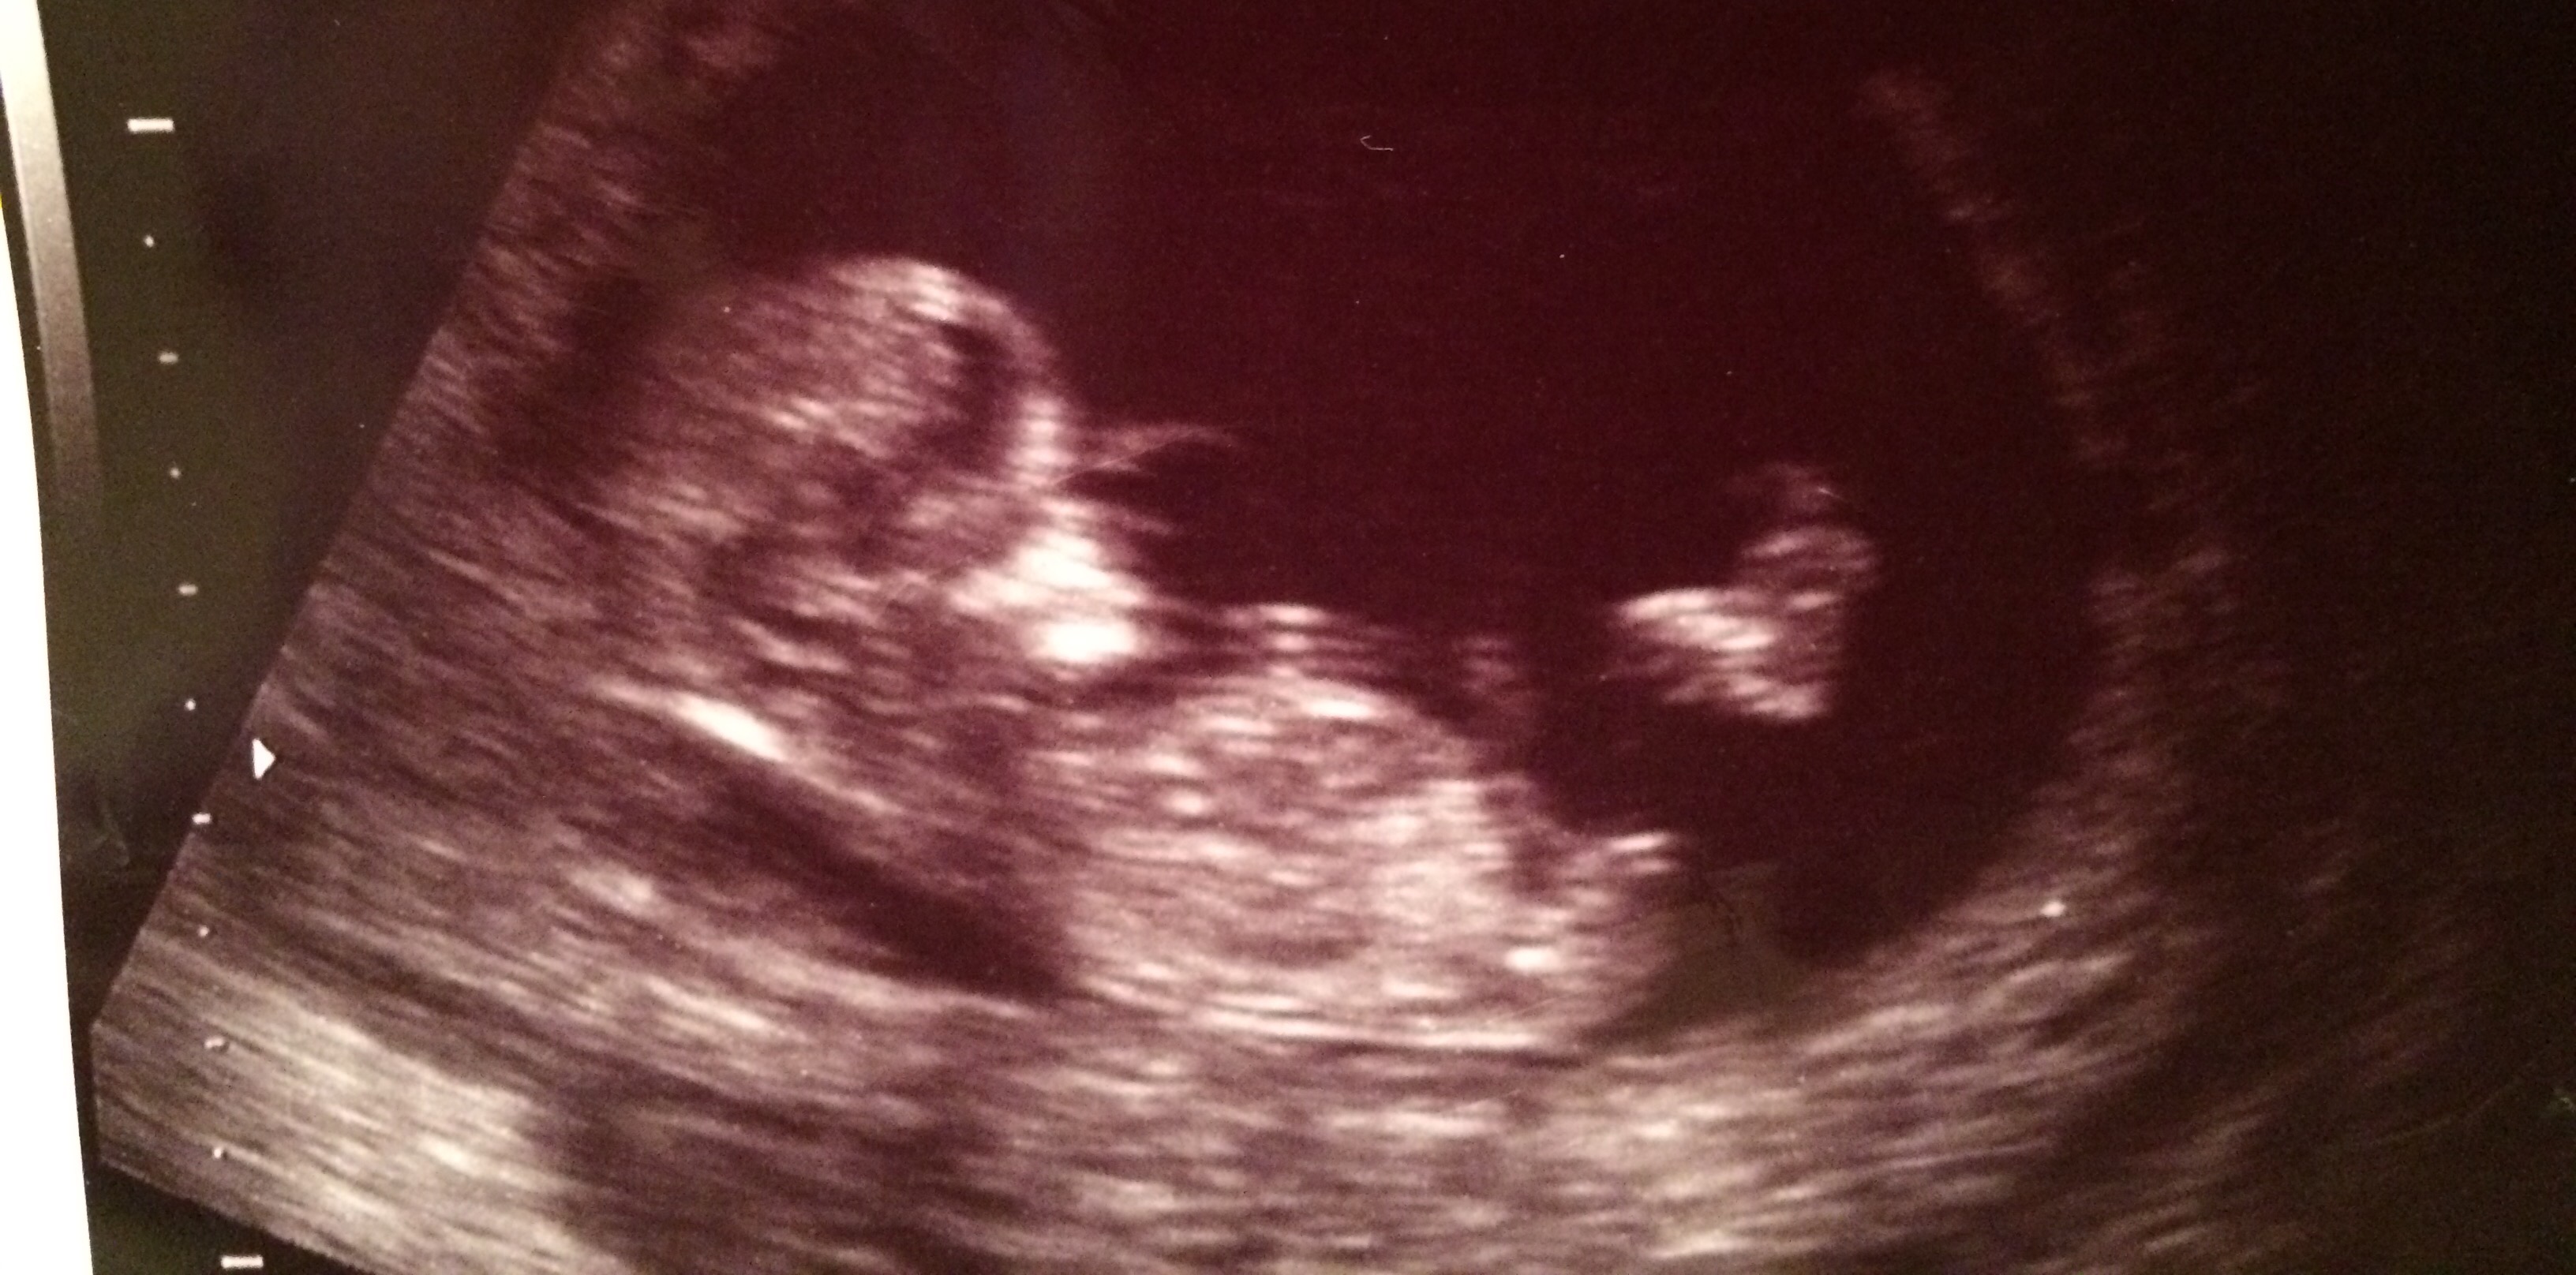

Let me know if you have any guesses on my friend's 12 week ultrasound. Thank you!! Attachment 29327

I think there's an angle to the nub and at 12 weeks could rise more I'd lean boy x

Boy lean

Thinking boy x